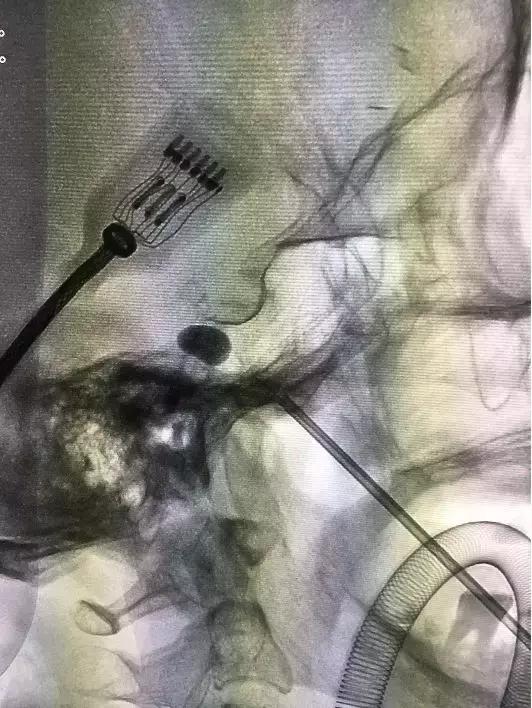

这个手术的核心*器武**就在于一根15厘米长的套管针,手术时要全麻,在神经介入导管室进行,医生从她左嘴角边上2.5厘米的地方将针穿进,通过神经介入DSA设备多角度透视定位,安全引导套管针到达颅内三叉神经根部,然后将针芯抽出,采用神经介入导管操作技术把跟水笔笔头差不多大的球囊通过管道塞到根部,向球囊注射造影剂扩张,持续压迫神经5分钟,使神经发生变化,传导受限,达到治疗效果。

左侧口角外穿刺定位

术中穿刺套管针到位

方奶奶欣然接受了这种方法,5月上旬,通过潘剑威主任医师和沈建副主任医师30分钟的手术,术后疼痛感完全消失。